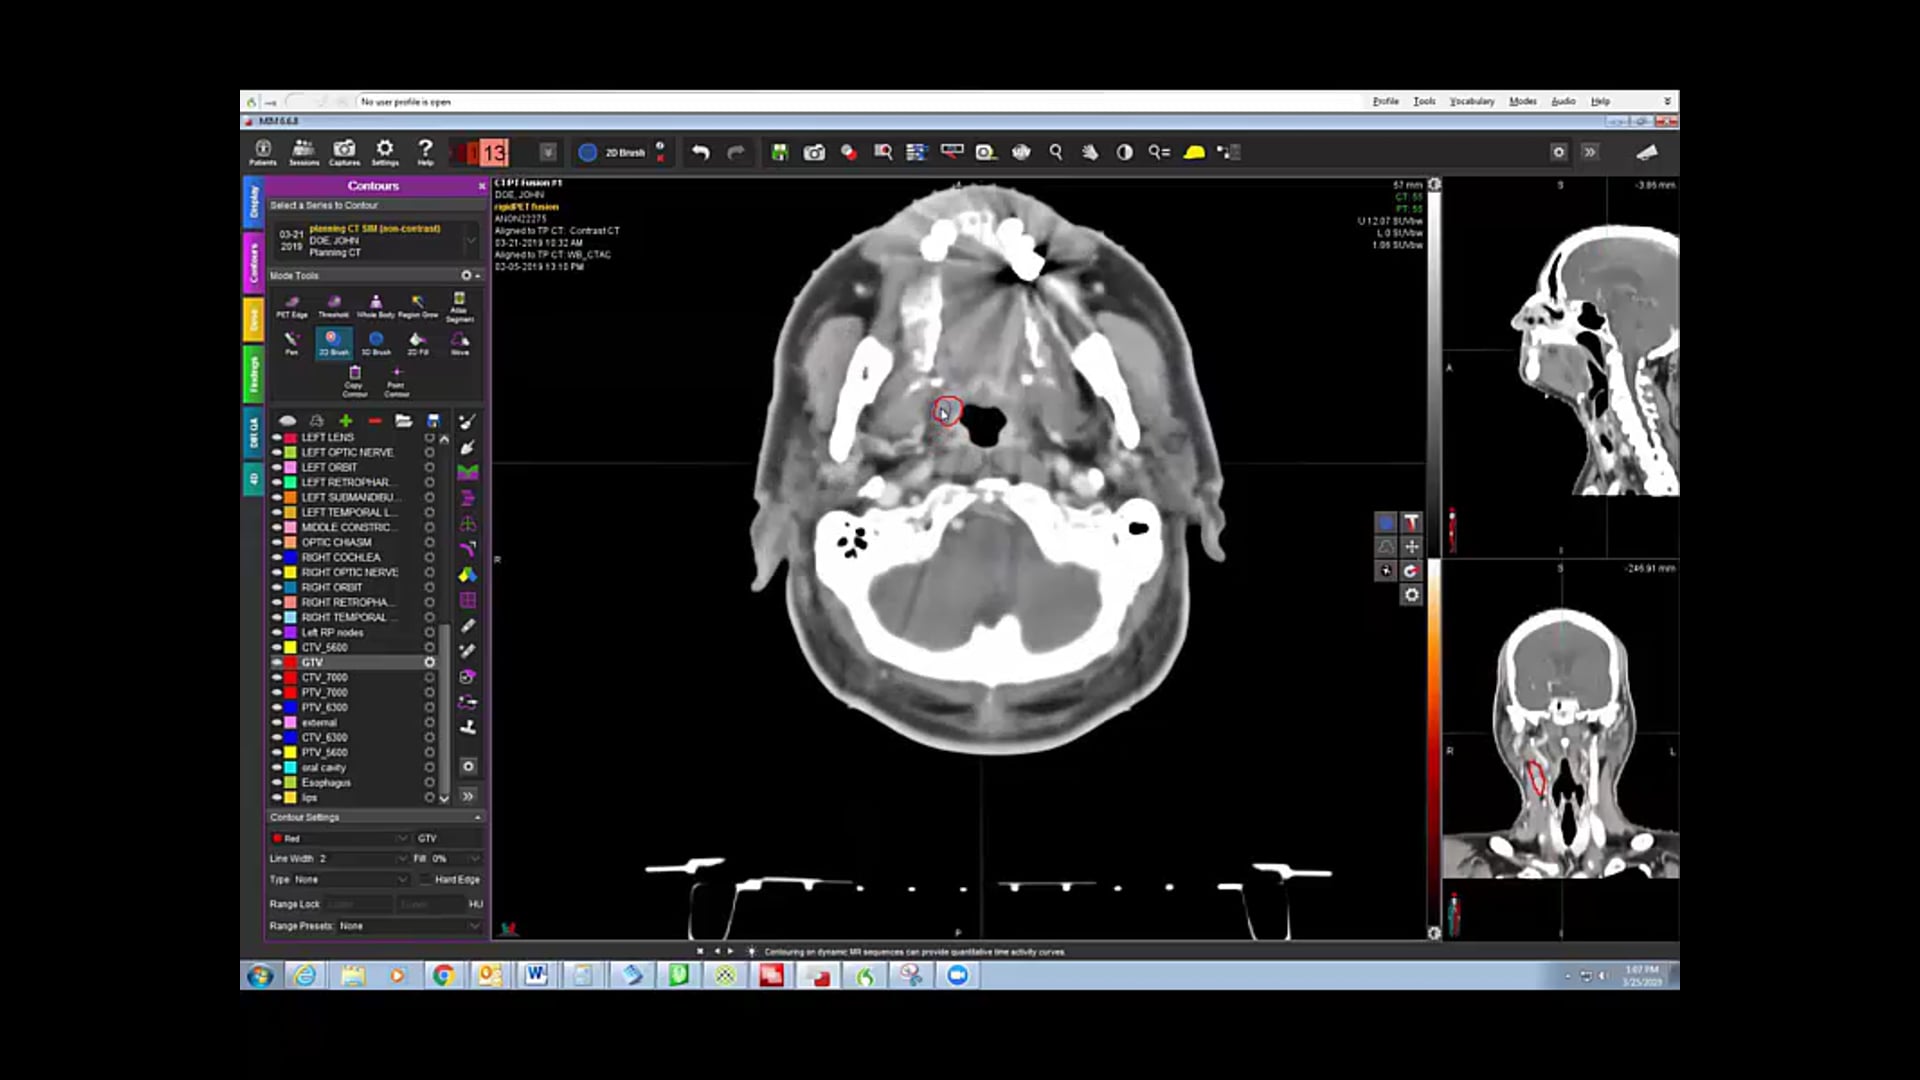

03/08/19 - Dr. Kenneth Hu - Radiation Oncology - Head and Neck US

-